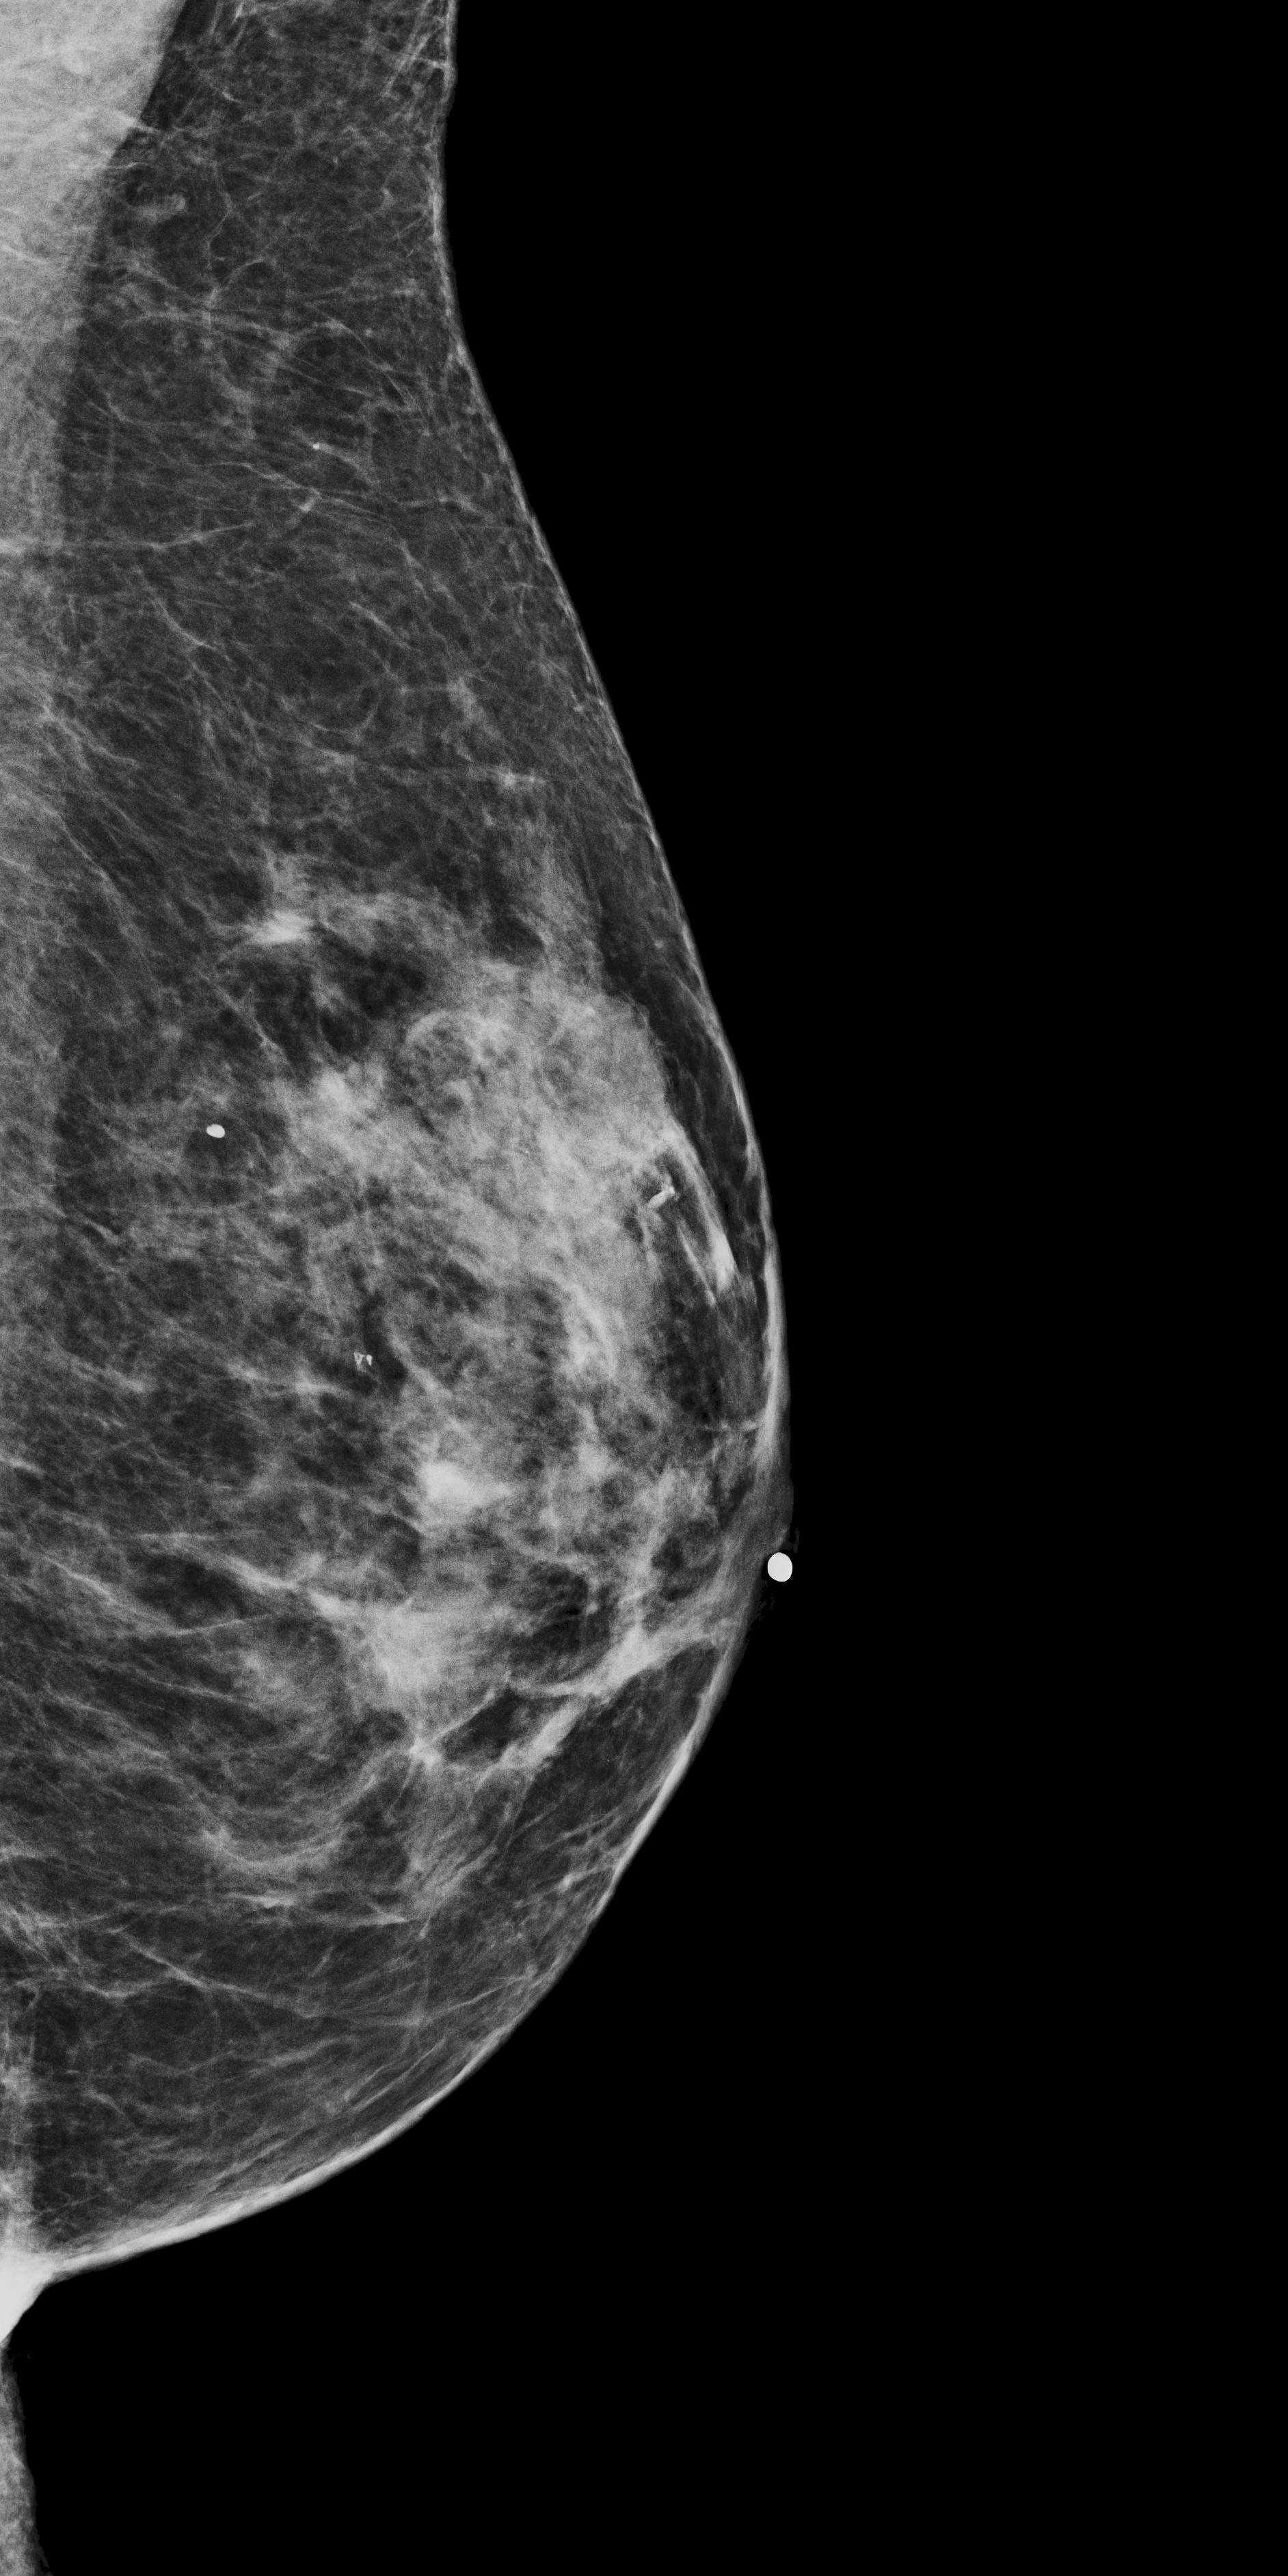

The methodology presented in Patch-DM [4] is closest to the proposed approach. It focuses on synthesizing high-resolution natural images using a patch-based approach and a denoising diffusion model. Unlike MAMBO, which works in pixel space, Patch-DM constructs images by independently denoising patches and composing them in feature space using positional embeddings. Pretrained CLIP [29] is used to obtain initial global context embeddings, which are later optimized during the training. To explore Patch-DM’s potential in the medical domain, we trained it on mammography data to generate images using its original settings with a patch size of pixels, and we use Mammo-CLIP [8] as a pretrained model for obtaining the initial image embeddings. The model was trained for more than two weeks on two NVIDIA A100 GPUs, during which it was exposed to more than 15.5 million mammography images. Despite this extensive training, Patch-DM still struggles to reproduce globally coherent and anatomically realistic mammograms, as shown in Fig. 3(e). This highlights both the limitations of the model in capturing domain-specific structure and its substantial computational demands.

4.1.3 Qualitative Results

The baseline for this task is a single-channel U-Net-based DDPM trained on full-resolution -pixel patches extracted from mammograms. This model learns patch characteristics but performs poorly in image reconstruction tasks. Even if the patch is not generated from pure noise but from the partially noisy patch of an original image, the reconstruction is poor, as shown in Fig. 3(c).

What MAMBO can achieve in terms of qualitative results is presented in Fig. 1 and Fig. 3(d). MAMBO is able to generate high-quality images that are visually indistinguishable from the originals, representing plausible mammogram data to layman eyes. Results are also validated with expert radiologists, with quantitative results shown in Sec. 4.2.

Fig. 3(d) illustrates what MAMBO can achieve in terms of whole mammogram generation. When using global and local context data extracted from an original image, the denoised image (Fig. 3(b)) is difficult to distinguish from the original (shown in Fig. 3(a)). When providing only the original global context and generating local context and target patches from noise, we still observe good results, as we show in Fig. 3(d).